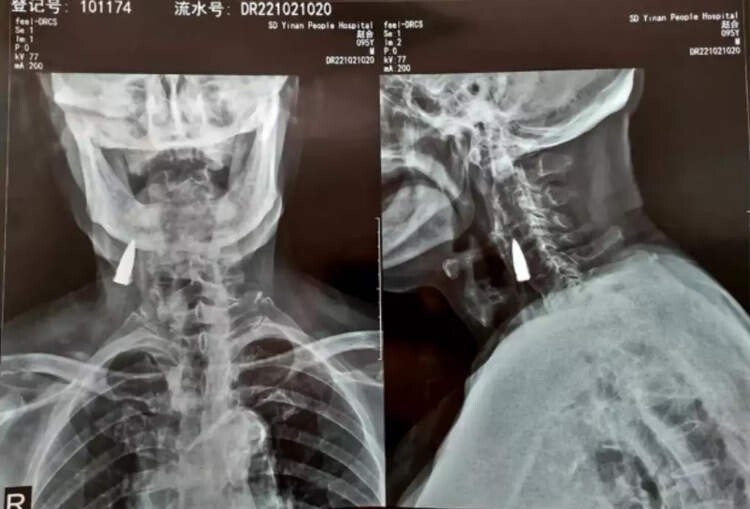

Після падіння з балкона свого будинку в китайській провінції Шаньдун, Чжао Хе, гніваючи на свій поважний вік, почував себе нормально - по принаймні, як кажуть його рідні, він не повідомляв їм про будь-які симптоми. Болю він не відчував, але через деякий час у ветерана Другої світової війни з'явився легкий дискомфорт у шиї. Син вирішив відвезти його до лікарні на обстеження. Почувши про його падіння, лікарі порекомендували зробити рентген, щоб переконатися, що він не отримав серйозні пошкодження шиї. Однак замість перелому рентген виявив у шиї у чоловіки сторонній предмет, який пізніше ідентифікували як стару кулю.

Сам Чжао вважає, що куля перебувала у його шиї з 1944 року. Очевидно, вона справді потрапила до нього переході через річку. Куля пройшла через ліву частину носа, пробила йому верхню щелепу та вибила кілька зубів, після чого застрягла у шиї. Втім, це лише його здогад.

Вивчивши рентгенівські знімки, лікарі сказали Чжао Хе та його родині, що куля пройшла поряд з деякими великими кровоносними судинами і що, оскільки вона не викликала у нього жодних проблем, краще залишити її, як є. Ветеран війни погодився. «Я був здоровий усі ці роки, тому зараз немає причин щось міняти», - сказав Чжао Хе.